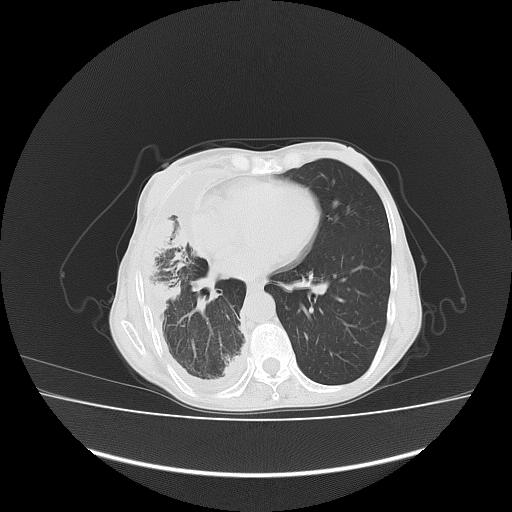

标题: CT16930:女 59 胸痛6个月 胸水脱落细胞学见瘤细胞 [打印本页]

可见多发肺内病灶,且胸膜病灶较多有圆球状而非丘状,多考虑胸膜转移瘤伴胸腔积液,右侧胸廓缩小固定,且部分病灶呈丘状,尚不除外恶性胸膜间皮瘤伴肺内转移

右侧胸膜增厚,局部呈结节状增厚,右侧胸腔少量积液。双肺未见确切肿块影。纵隔未见淋巴结肿大。气管、支气管通畅。考虑右侧胸膜间皮瘤(恶性?)可能性大。不除外癌性胸膜炎。

恶性胸膜间皮瘤伴肺内转移可能性大;或胸膜、肺内均为转移瘤,左肺下叶亦见多发小结节影。

右侧胸廓塌陷,右侧胸膜广泛增厚并见多发胸膜结节,右侧少量胸腔积液并包裹。

右侧广泛胸膜增厚,局部呈结节状增厚,右侧胸腔少量积液。双肺未见确切肿块影。纵隔未见淋巴结肿大。气管、支气管通畅。考虑右侧胸膜间皮瘤(恶性?)可能性大。支持!

右侧胸膜转移瘤,原发灶可能就在在右肺,另外建议检查右侧乳腺.

右胸腔结节均考虑来自胸膜(部分来源于叶裂),考虑胸膜间皮瘤或转移瘤.